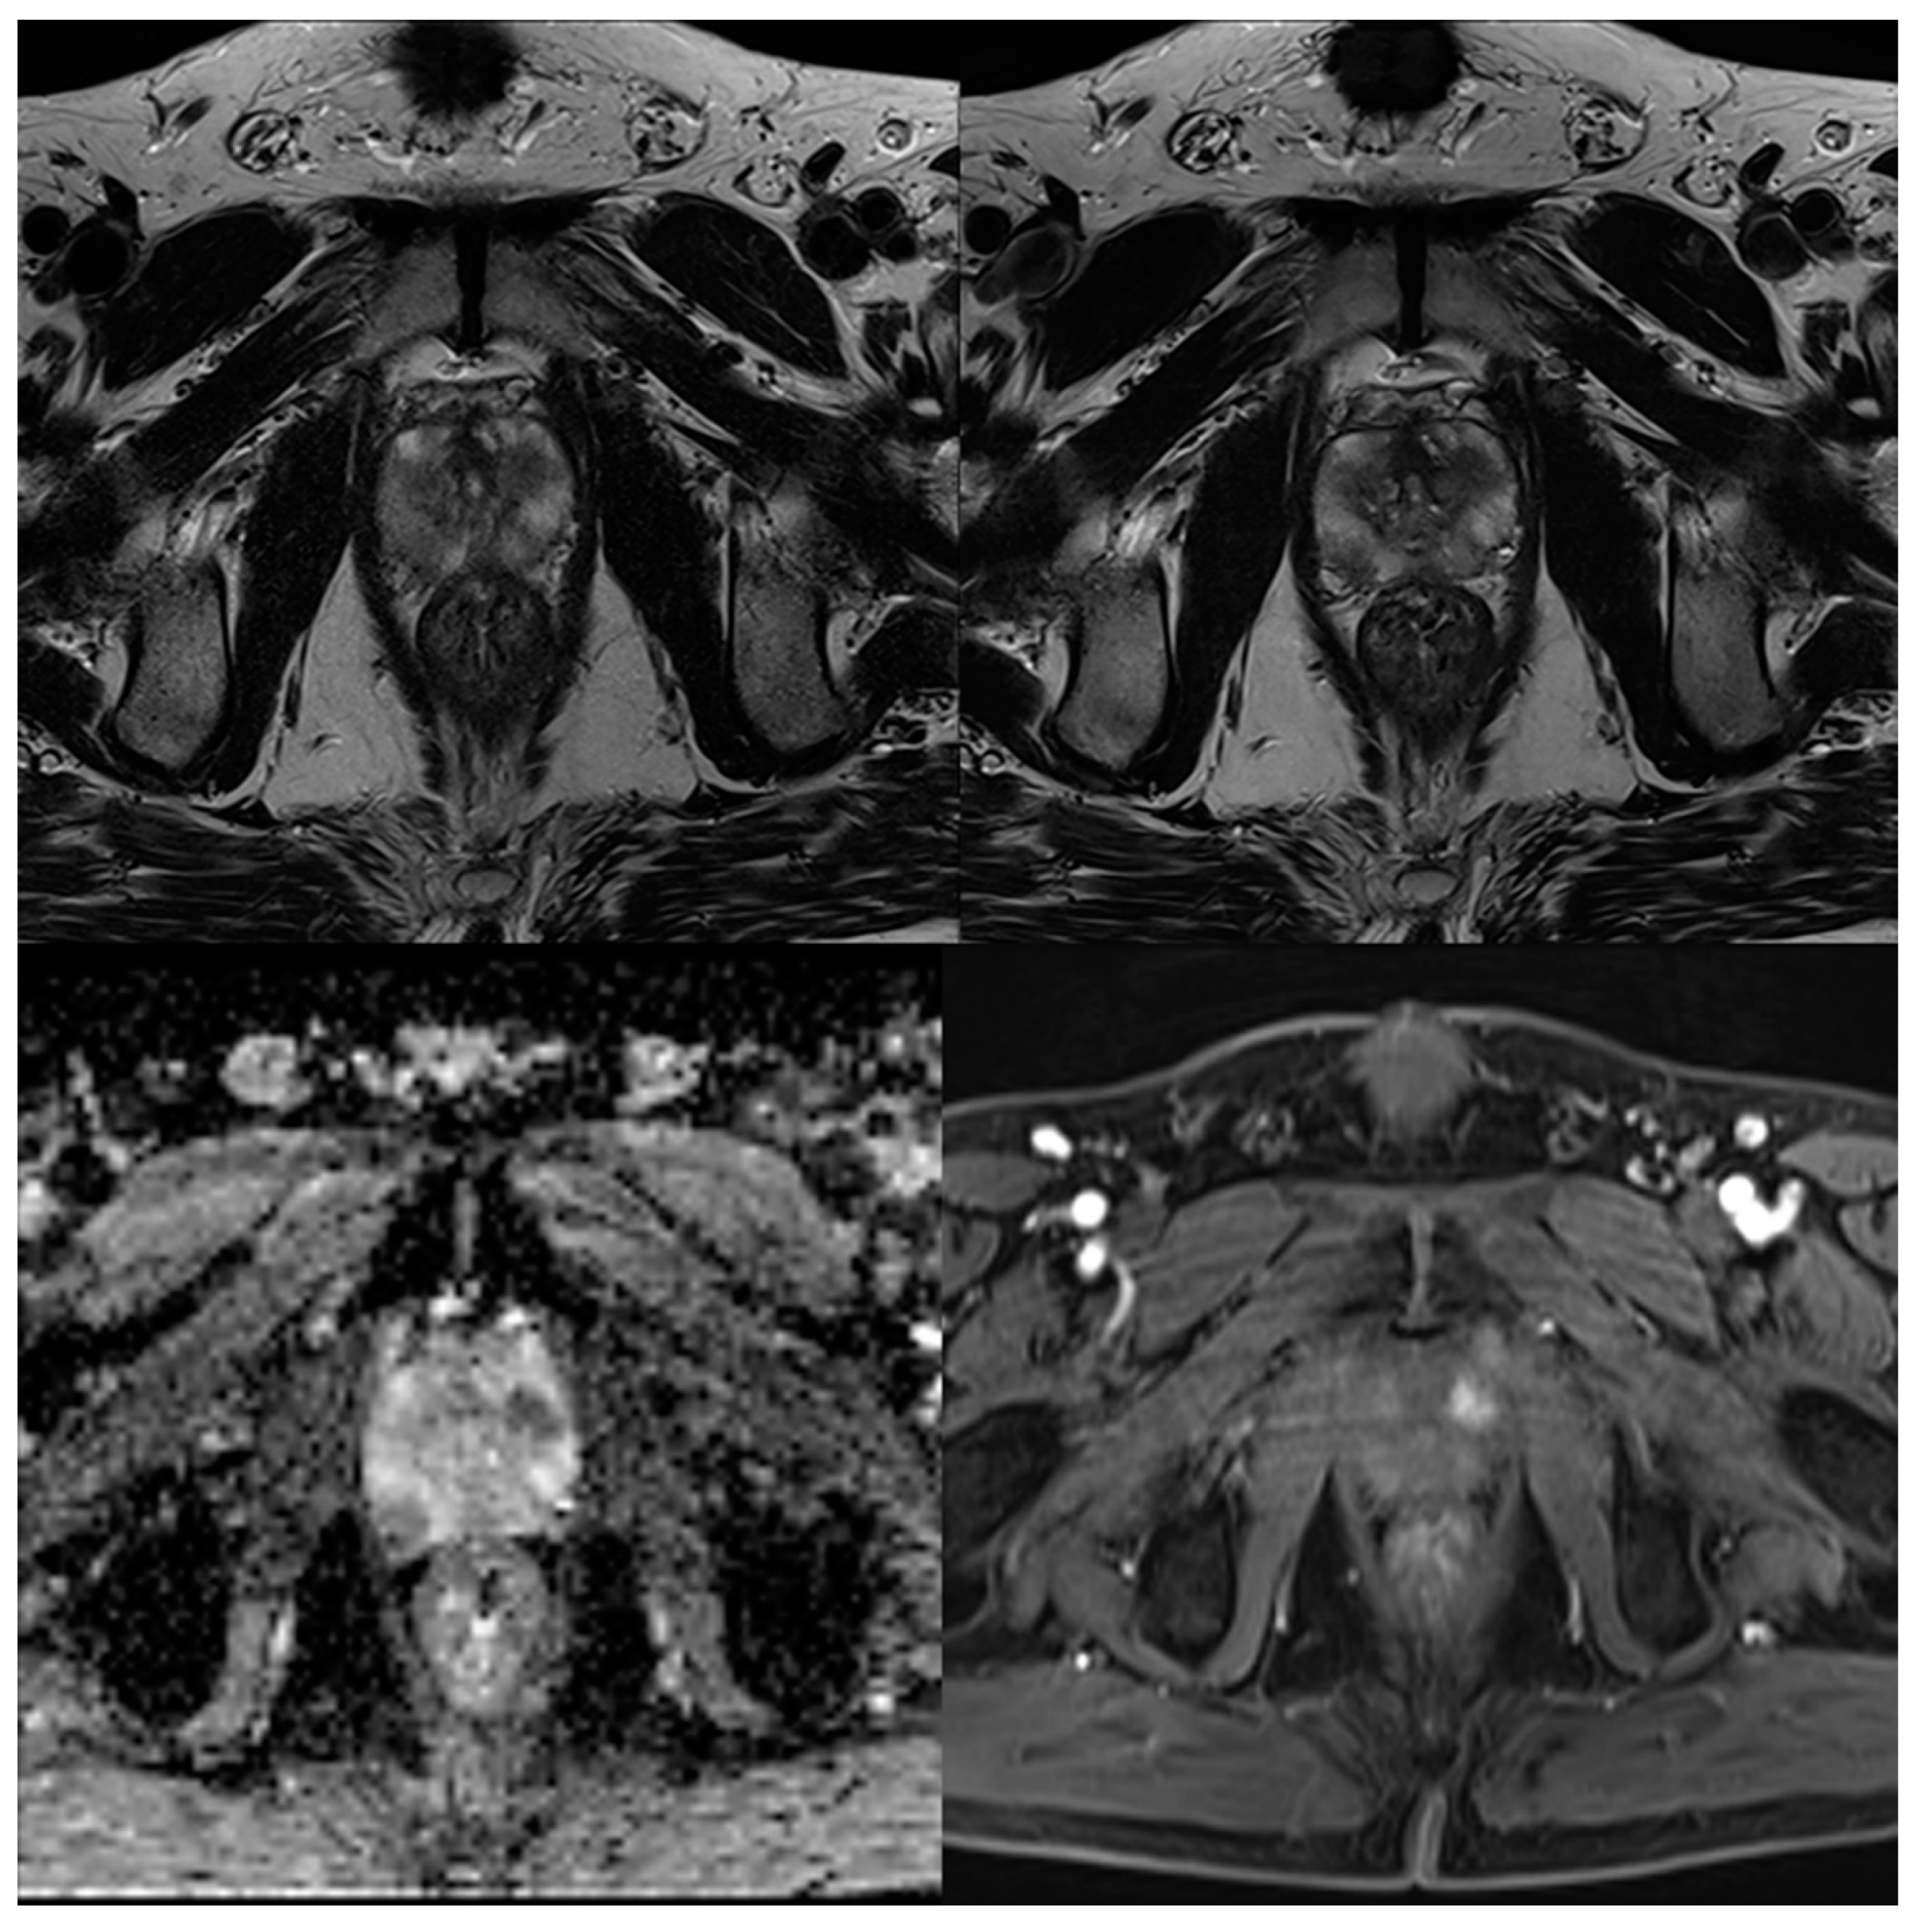

Figure 5. A 76-year-old male patient with suspicion of prostate cancer. Example of sagittal standard T2-weighted TSE imaging (T2S) on the left-hand side and deep learning–reconstructed (T2DLR) imaging on the right-hand side. This figure demonstrates the advantages of deep learning image reconstruction, regarding image noise and sharpness of organ structures.